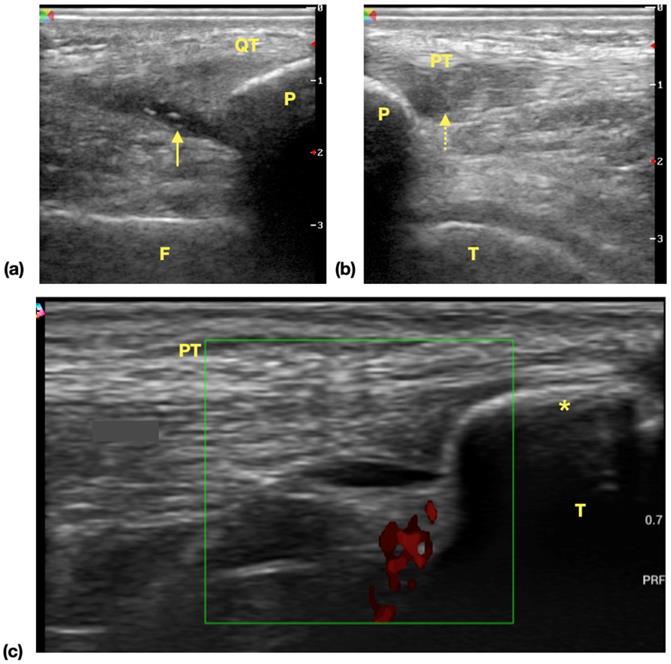

The result of ultrasonography examination (Table 3) showed significantly higher incidence of at least one positive findings among player groups compared with control group [28 (73.68%) vs 2 (6.67%), P<0.01] and also the incidence of at least one ultrasonographic finding among all screened areas [40/266 (15.04%) vs 2/210 (0.95%), P<0.01]. In all identified lesions in ultrasonography, the incidence of suprapatellar recess effusion [21 (55.26%) vs 0 (0.00%) P<0.01] and patellar tendon lesions [6 (15.79%) vs 0 (0.00%), P=0.03] are higher in player groups (Examples of ultrasonographic findings were shown in Figure 1). There was no difference in the incidence of medial collateral ligament lesions [6 (15.79%) vs 1 (3.33%), P=0.12], tibial tuberosity apophysitis [3 (7.89%) vs 1 (3.33%), P=0.62], lesions at iliotibial band insertion [2 (5.26%) vs 0 (0.00%), P=0.50] or distal quadriceps tendon lesions [2 (5.26%) vs 0 (0.00%), P=0.50]. There was no evidence of lateral collateral ligament injury in both the players and control group subjects. We also found out that in players and control group subjects, the incidence of positive ultrasonography lesion is significantly higher [68% (13/19) vs 4% (1/25), P<0.01] in player group. For the subgroup analysis of player group, the scores of IKDC-SKF with positive (n=26) and negative ultrasonography examination findings were compared and the result showed no difference between these groups (IKDC-SKF score 75.31±2.94 vs 81.58±3.39, P=0.21).

Figure 1

Common ultrasonographic findings of knee in surveyed athletes. (a) Effusion of suprapatellar recess. Hypoechoic area (arrow) is noticed in the extent of suprapatellar recess and the findings is suggestive of suprapatellar recess effusion. (b) Patellar tendinopathy. Focal hypoechoic change and swelling of proximal tendon is noticed. The normal fibrillar pattern of echogenicity is disrupted (dotted arrow) (c) Tibial tuberosity apophysitis. A separated bone fragment (asterisk) apart from tibia bone is noticed, and power doppler shows increased signals, which is suggestive of inflammatory process. Abbreviations: QT: quadriceps tendon, F: femur, P: patella, arrow: effusion, PT: patellar tendon, T: tibia.